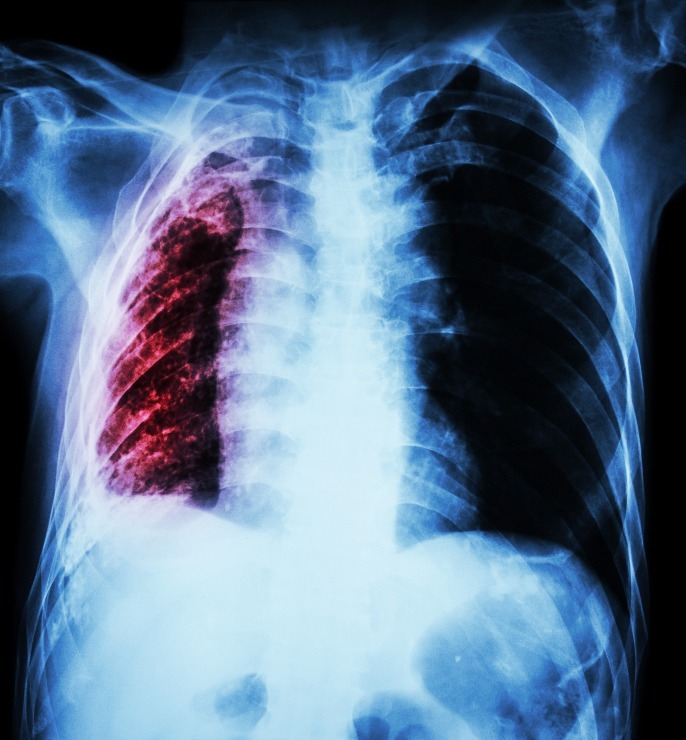

Tuberkulózou se nenakazíte snadno

Tuberkulóza, známá též jako TB, je infekční onemocnění, způsobené bakterií Mycobacterium tuberculosis. Často postihuje plíce, ale může ovlivnit i jiné části těla. Přenos probíhá vzduchem, když infikovaná osoba kašle, kýchá nebo plive. Nemoc je léčitelná a prevence je možná, tuberkulóza však přesto zůstává jedním z předních infekčních zabijáků na světě, s miliony nových případů každý rok. Naštěstí se jí nenakazíte tak snadno.

Symptomy aktivní tuberkulózy mohou zahrnovat dlouhotrvající kašel, krev ve vykašlaném hlenu, bolesti na hrudi, horečku, noční poty, úbytek hmotnosti a celkovou únavu. I když může TB zůstat latentní – bez projevů symptomů, aktivní forma je vysoce infekční a bez adekvátní léčby potenciálně smrtelná.

Historie tuberkulózy je dlouhá a komplexní, s doloženými případy již ve starověkém Egyptě. V 19. a 20. století se tuberkulóza stala pandemickou, což bylo dáno tehdejšími socioekonomickými podmínkami. Vývoj léků a vakcín proti TB způsobil významný pokles počtu případů v mnoha zemích, avšak stále představuje globální zdravotní hrozbu, zejména v rozvojových zemích a v populacích s častým výskytem HIV. Podle Světové zdravotnické organizace zemřelo v roce 2022 na tuberkulózu 1,3 milionu lidí, což ji činí jedním z předních infekčních zabijáků na světě.

V České republice je situace s tuberkulózou optimističtější; počet nových případů nadále klesá. Většina pacientů s tuberkulózou je starší 65 let, nebo se jedná o osoby v určitých rizikových skupinách. I v Česku však mírně roste počet pacientů s multirezistentní tuberkulózou, která nereaguje na terapii standardními léky. Tato forma TB vyžaduje delší a komplexnější léčbu, která může trvat až dva roky.